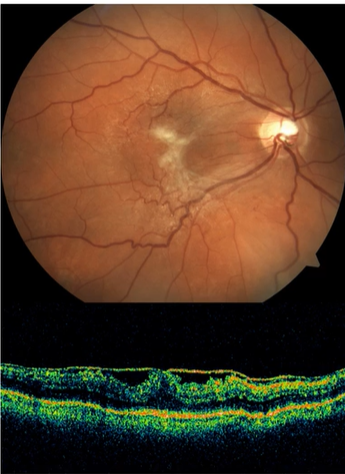

Name the condition

CSR

Central Serous Chorioretinopathy- CSCR/CSR

Symptoms

Clinical signs

Investigations

Management

Decreased, blurred vision

Metamorphopsia

Central defect in the visual field

Colours appears washed-out

Usually unilateral sometimes bilat

Localised elevation of the retina in the macular region

Focal hyperpigmentation (sign of previous episodes)

Fluorescein angiography (“smoke- stack” , “ink-blot” leakage)

Neovasc

Usually not required (most cases [~80%] recover in ~6-9months)

Laser treatment may be considered